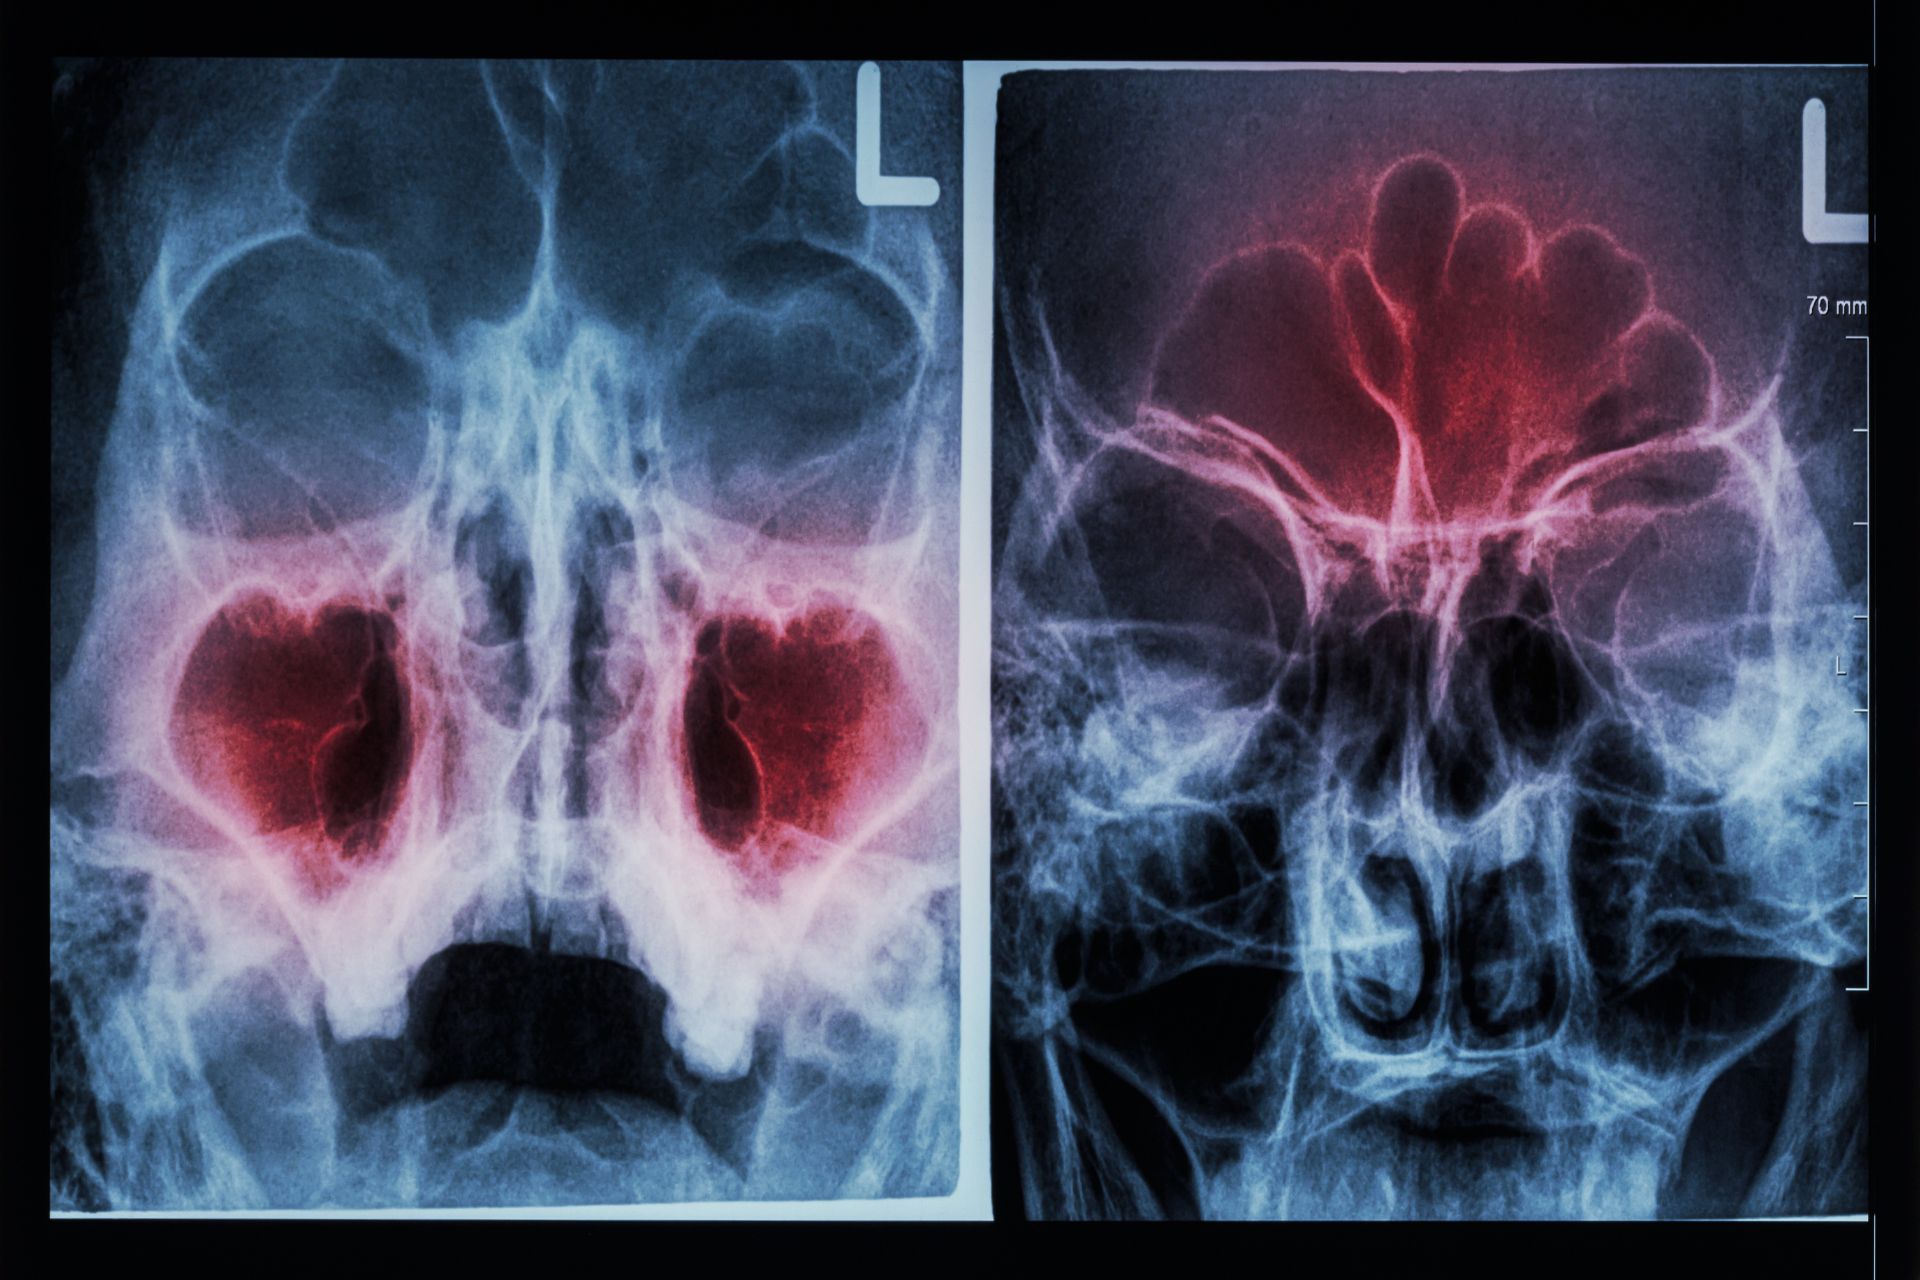

This technologically advanced technique improves improves the accuracy and safety of sinus surgery, decreasing the risk of damage to the brain, eye, nerves, and blood vessels leading to safer and more effective outcomes for our patients.

Safety and Precision at the Forefront